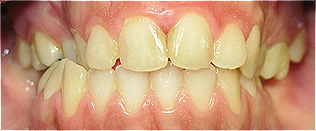

Apinhamento dentário com os dentes caninos em desoclusão (classe II, divisão 2).

![]() |

Após dois anos de tratamento ortodôntico.